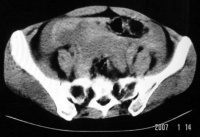

3.CT表现:

(1)输卵管积液或输卵管卵巢囊肿在大多数病例中不能与其他囊性肿块鉴别。

(2)输卵管-卵巢脓肿直径需>2cm以上CT才易于显示,表现为混杂密度肿块,边缘光滑或有毛刺,壁厚而不规则,脓肿壁在增强后比一般囊肿有更明显的强化。当囊内有气体存在时,对诊断脓肿有帮助。

(3)积液时CT值为0~15HU,积脓时CT值为15~40HU。